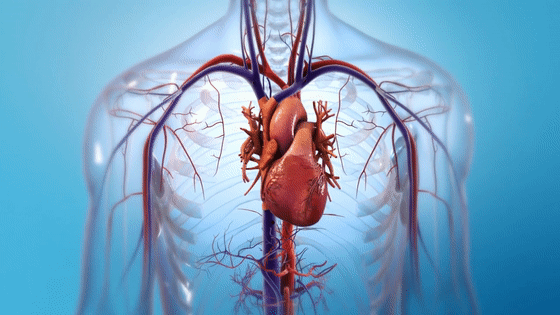

心脏跳动模拟

05真实的心脏跳动示意图

08心脏泵血图

12心脏跳动三维透视图